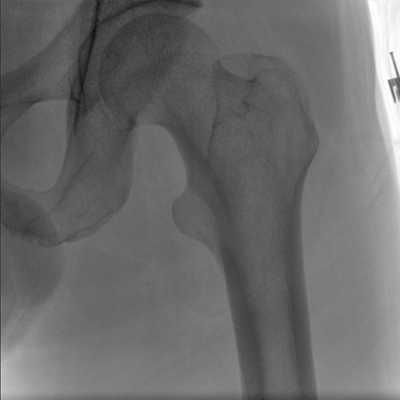

临床适用科室:骨科、普通外科、矫形外科、创伤外科、泌尿外科、脊柱外科、疼痛外科、消化科、妇科等科室。

大尺寸动态平板探测器,高DQE、低噪声、图像清晰。采用多分辨率图像增强处理技术,不同部位不同图像处理算法,满足客户多样化的需求。

多角度自由旋转,满足患者复杂摆位需求。